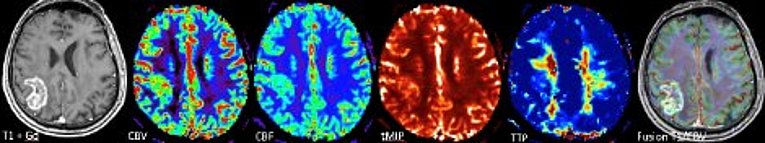

Multiparametrische Bildgebungsverfahren wie die spezielle Diffusions-, Perfusions- und quantitative (suszeptibilitätsgewichtete) MRT-Bildgebung ermöglichen dabei eine „state-of-art“ Betreuung unserer Patientinnen und Patienten hinsichtlich Erstdiagnose (Befundeinordung, „Differentialdiagnose“) und insbesondere in der zuverlässigen Verlaufsbeurteilung von Hirntumoren.

Die multiparametrische Hochfeld-MRT kann zum Beispiel Neovaskularisation, Wachstumsdynamik und Metabolismus (Nekrose, Progression, Pseudoprogression, Pseudo-Response) von Hirntumoren charakterisieren. Der multiparametrische Ansatz ermöglich es dabei sogar, „Imaging-Biomarker“ für die pathophysiologischen Prozesse auf zellulärer Ebene zu identifizieren. Aufbauend auf unseren umfangreichen experimentellen und klinischen Vorarbeiten nutzen wir für den Transfer der Ergebnisse in die klinische Anwendung auch innovative KI-Verfahren.

Blutgefäße spielen eine entscheidende Rolle im Entwicklungsverlauf bösartiger Tumore. Im frühen Stadium der Tumorentwicklung wachsen die meisten Läsionen avaskulär bis ein Gleichgewicht zwischen Proliferation und Apoptose erreicht ist, danach setzt meist Neoangiogenese ein. Der Grad der Vaskularisierung korreliert dabei mit der Tumoraggressivität sowie schlechter Prognose beziehungsweise Outcome. Eine Beurteilung der Architektur des Tumorgefäßbetts ist daher von hoher Relevanz für die klinische Beurteilung und der Therapieplanung von Hirntumoren. In interdisziplinärer Zusammenarbeit mit der Neurochirurgischen Klinik und mit finanzieller Unterstützung der Deutschen Forschungsgemeinschaft und internationaler Beteiligung konnten neue Strategien der MRT-Bildgebung und der Bildverarbeitung zur Darstellung der Neovaskularisation von Hirntumoren entwickelt werden. So können neuartige Bewertungsstrategien von MR-Perfusionsdaten und neue MRI-Biomarker etabliert werden, die detailliertere Einblicke in die Komplexität und Heterogenität vaskulärer Veränderungen bei Hirntumoren liefern. Erste Ergebnisse von Untersuchungen bei Patienten mit rezidivierenden Glioblastomen während einer antiangiogenen Monotherapie (Bevacizumab) zeigen dabei, dass die frühe Reaktion (nach einem Monat) auf Bevacizumab durch die Reduktion der kleineren Mikrovaskulatur (etwa 10 μm) dominiert wird. In der 3-Monats-Kontrolle zeigt sich bei den Tumoren zusätzlich eine Reduktion der größeren Mikrovaskulatur (> 20 μm).